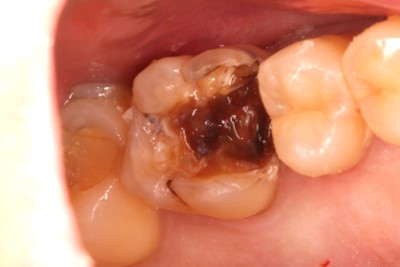

• 治療前

• 治療後